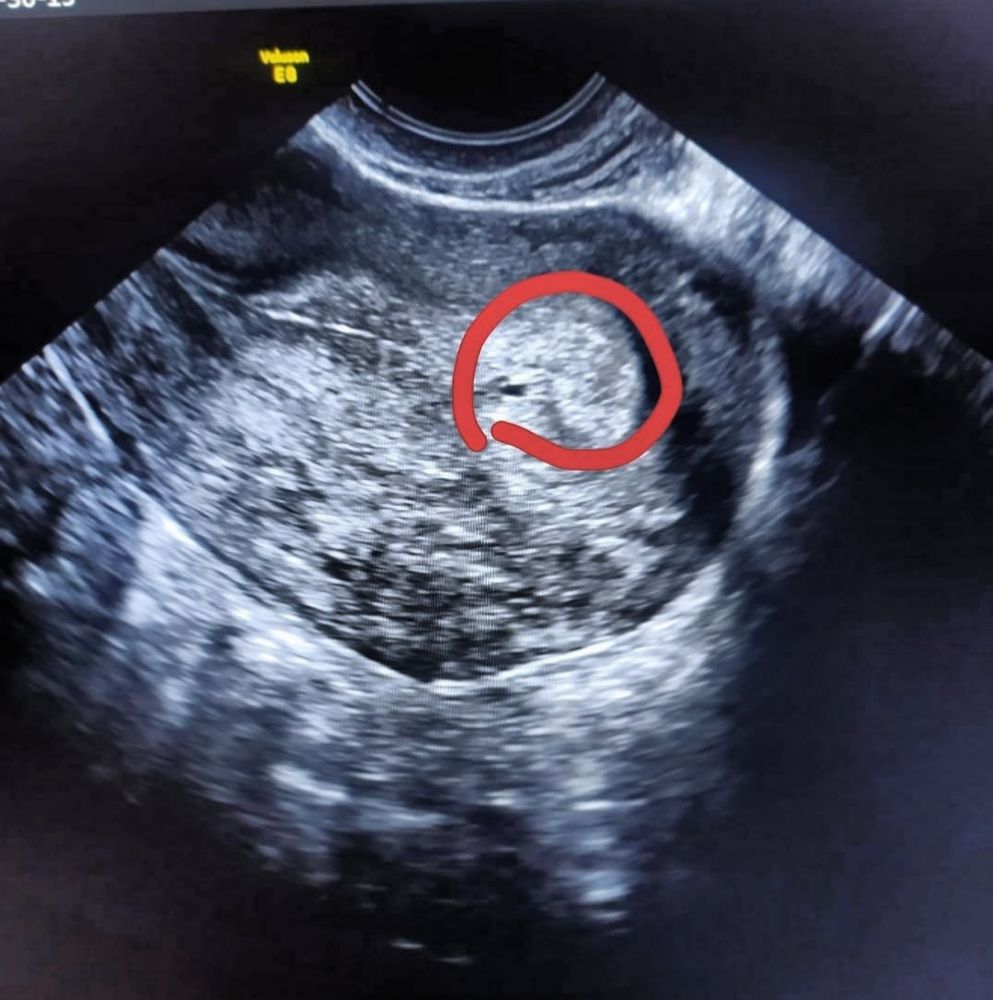

Васёна, два дня назад был 117 сегодня пя 1.5мм нашли на УЗИ ☺️ Изображение